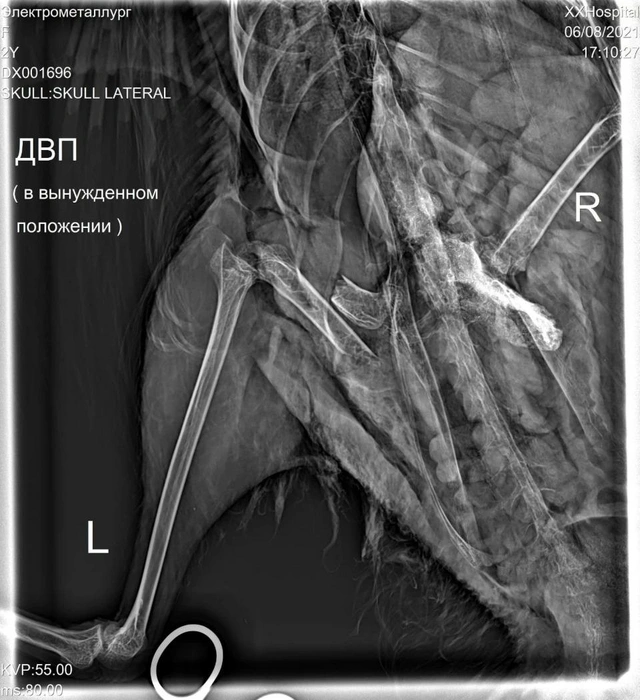

— Сначала мы обрабатывали и зашивали множественные укушенные раны на спине. Сейчас там всё зажило, всё чисто. Состояние лебедя — стабильно тяжелое, — рассказал Карен Даллакян. — Скорее всего, завтра будем делать вторую операцию, ждать уже некуда. Вмешательство предстоит тяжелое, с наркозом, а птица слабая, она может не выдержать нагрузку. Но у нее такое неестественное положение, она не может двигаться, только лежит на животе. Для водоплавающих это очень нехорошо, когда они не двигаются в воде. Наш лебедь не может плавать — на бок падает и из-за этого может даже утонуть.

По словам зоозащитника, лапа не только сломана. На ней множество гематом от укусов. Гематомы планируют вычистить, кость зафиксировать и установить дренаж, чтобы отходила жидкость.

— Там очень большой отек, припухлость и болезненность, — описал состояние лапы лебедя Карен Даллакян. — Повреждения такие, как от укусов крупных собак размером с овчарку, хаски или лайку. Чтобы сломать лапку лебедю, надо иметь мощную челюсть. Птица отказывается есть, хотя у нее целое меню: и овощи, и насекомые, и рыба, и зерновые. Всё что душе угодно. Но, к сожалению, кроме воды, она ничего не принимает. Это нехороший признак, поддерживаем ее медикаментозно.